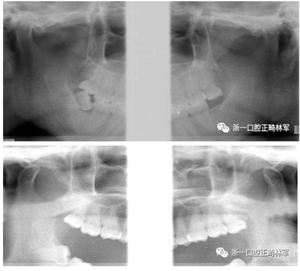

口內(nèi)檢查

2.png

恒牙列。上下頜中線對齊。上下頜牙列輕度擁擠。前牙覆合、覆蓋正常。尖牙、磨牙中性關(guān)系。上下前牙基本直立,前牙區(qū)牙根、牙槽骨較突。雙側(cè)上頜尖牙磨耗。

功能及顳下頜關(guān)節(jié)檢查:無關(guān)節(jié)壓痛及彈響,開口度、開口型正常。

X線片檢查分析

初診全景片:牙齒數(shù)目形態(tài)未見異常,牙根未見異常。48近中阻生。

初診張閉口關(guān)節(jié)片:張閉口位關(guān)節(jié)間隙正常。雙側(cè)髁突外形正常,骨皮質(zhì)連續(xù),未見明顯吸收變形。